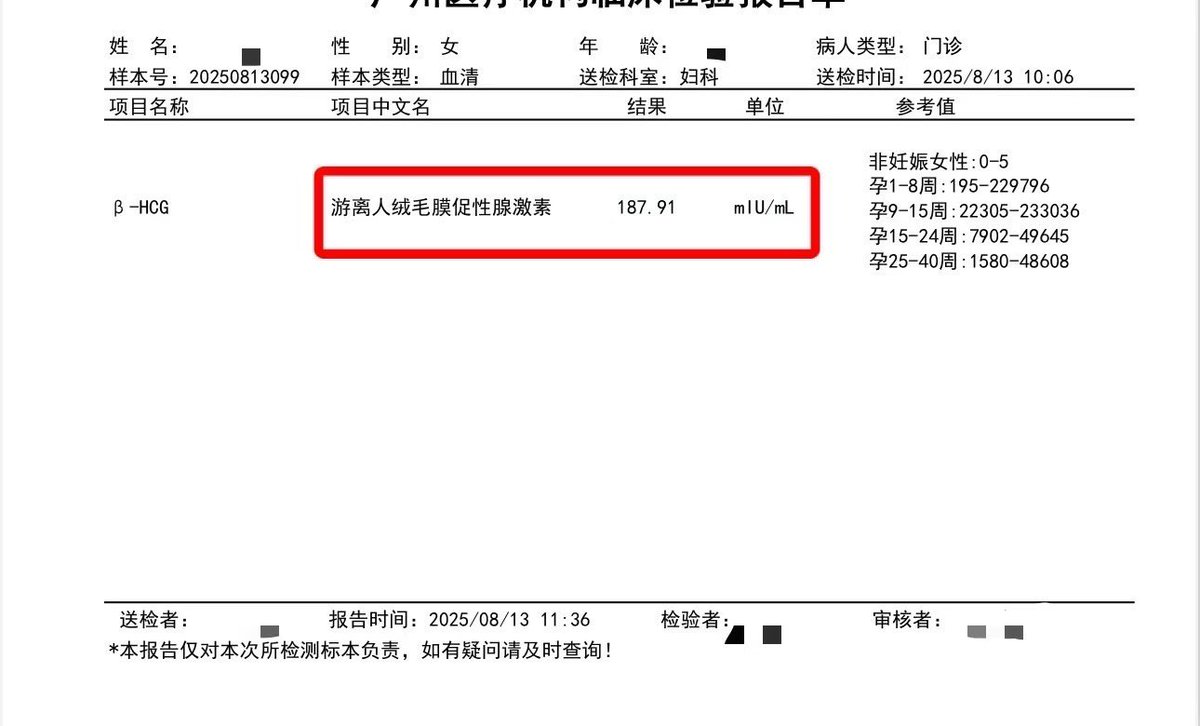

![代孕.HIV.洗精.国内代孕机构 (@wangjb168) on Twitter photo 【等待篇】

单胎11周 复查结果正常[庆祝]

专业试管代孕咨询微信:a18025307951

#试管婴儿 #试管助孕 #代孕 #广州代孕 【等待篇】

单胎11周 复查结果正常[庆祝]

专业试管代孕咨询微信:a18025307951